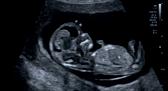

Een echografische afbeelding van een foetus tijdens het eerste trimester SEO onderzoek. Het onderscheidend vermogen van de echosystemen van Canon zorgt ervoor dat de echoscopist met vertrouwen het onderzoek uit kan voeren.

Een echografische afbeelding van een foetus tijdens het tweede trimester SEO onderzoek. Ook hier dragen hoogwaardige beeldkwaliteit en snelheid van het systeem bij aan het stellen van een betrouwbare diagnose.

Canon Medical Systems Nederland helpt u uw doelen te behalen. Wij zijn gespecialiseerd in het ontzorgen van al uw verplichtingen rondom uw Women’s Healthcare echografiesysteem. Zo heeft u meer tijd om optimale zorg te leveren aan uw patiënten.

U scant – Wij doen de rest!